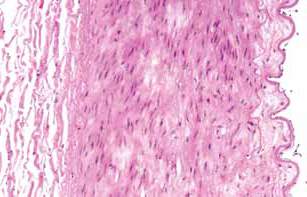

In a healthy artery, the lumen (dark center), where more apparent that like the heart, blood vessels

blood flows, is surrounded by arterial wall (red).

undergo changes with advancing age, and these

Age-related changes in the arteries, such as arterial changes, including arterial stiffening and thicken-thickening and stiffening, can make them more susing, are major risk factors for these diseases.

ceptible to cardiovascular diseases.

Adventitia

Media

Intima

Endothelium

A sectional view of the arterial wall. On the right aortic pulse wave velocity (aPWV) is an inde-is the intima, topped by a layer of cells called the pendent predictor of arterial stiffness and cardio-endothelium. The endothelium acts as a barrier to vascular disease and death.

prevent certain substances from entering the vessel wall. In the center, the media is composed of

As the walls of the large arteries become stiffer,

smooth muscle cells and a network of fibrous pro-

diastolic blood pressure tends to drop and systolic

teins. The outermost layer, the adventitia, is com-blood pressure rises. The difference between these

posed of connective tissue.